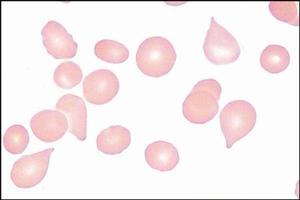

紅細胞形態發生各種明顯改變的情況而言,可呈淚滴狀、梨形、棍棒形、新月形等,最常見於巨幼細胞性貧血。而淚滴狀紅細胞就是指紅細胞外形象淚滴狀或梨形,是正色素性的。

簡介 原理 構成 特點 使用說明,如小細胞低色素紅細胞與缺鐵性貧血、大的橢圓形紅細胞與巨幼細胞性貧血、淚滴狀紅細胞與骨髓纖維化、小球形紅細胞與遺傳性球形紅細胞增多症或自身免疫性... 正常情況下紅細胞的生成與破壞維持平衡,單位體積血中的紅細胞才能恆定,一旦...

基本信息 內容介紹 作者簡介 目錄 書摘Hb 100~120g/L,紅細胞<2.0×10/L,紅細胞大小不等,呈小細胞低色素性貧血,中央淺染。外周血塗片紅細胞異形明顯,可見梨形、淚滴狀、小球形、三角形、靶形及碎片。嗜鹼性點彩紅細胞,多嗜性紅細胞,有核...